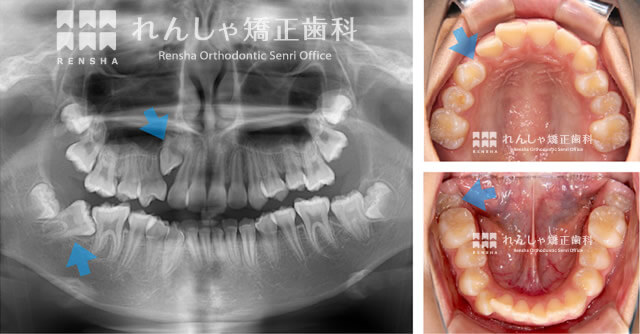

歯と歯列の大きさにアンバランスが生じると歯並びががたついてしまいます。Y.Kさんの場合、一見がたつきは少ないものの、スペースが不足したことで右上犬歯と右下奥歯が骨の中に埋まったままになっています。

このままでは歯並び、噛み合わせの機能、虫歯リスクの高まりなど様々な問題が起こってしまいます。

とくに右上の3番目(犬歯)は非常に深い位置に埋まっており、自然な萌出を期待していたのですが、なかなか降りてきません。そのため、引っ張り出すことができない恐れがあります。そこでご本人とご両親に、この犬歯を含めて数本の永久歯を抜歯する方法もご提案しました。

そこで埋まったままになりそうな右上犬歯と、右下奥歯のスペースの確保から開始することにしたのです。